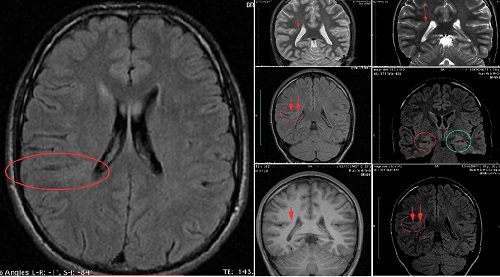

Magnetic Resonance (MRI)

MRI stands for Magnetic Resonance Imaging,a non-invasive diagnostic procedure that uses magnetic fields and radio frequencies to generate detailed anatomical and functional images. MRI scans have an advantage over some forms of scanning because they can image different types of organ tissue without ionizing radiation. More traditional forms of imaging, such as X-rays, are limited in how much tissue they can image.

Our MRI department is equipped with a GE Signa HD, 1.5T MRI scanner.

The Signa HDe 1.5T High-field MRI is engineered for enhanced image contrast, reduced blurring and reduced artifacts so your doctor can see more. This system also incorporates motion correction to help reduce the need for rescans. GE Signa HDe is a high resolution, whole body imaging system known for its excellent performance. The powerful magnetic resonance imaging platform provides high definition results and a comprehensive range of applications.